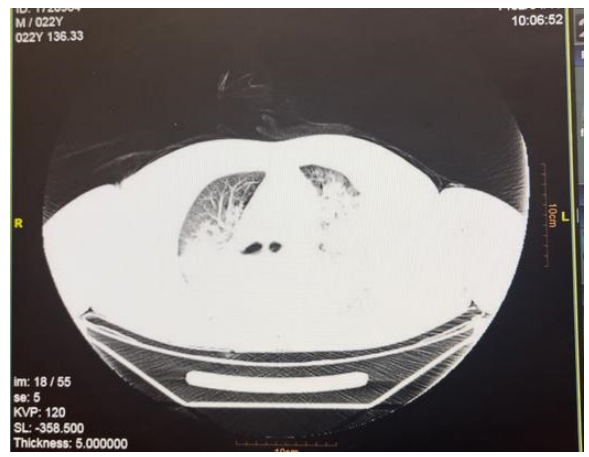

Following intubation, a lung CT scan (Figure. 1-A) revealed severe alveolar infiltration, and the patient was transferred to the Poisoning ICU ward. Despite receiving 100% oxygen (FiO2), oxygen saturation remained around 75% in SIMV mode with a PEEP of 5 cmH2O, Ti of 1.2 s ,TV of 500 ml, and airway secretion suctioning, which included significant pinkish fluid. His blood pressure and pulse rate were as follows: BP 93/40 mmHg, PR 112 bpm.

Figure 1-A: Chest CT Scan at Admission Day

A pulmonary CT scan revealed severe alveolar infiltration on both sides, while lab tests showed leukocytosis, high CRP levels, respiratory acidosis in VBG, and positive results for tetrahydrocannabinol and methadone in his screening test. Consequently, we initiated broad-spectrum antibiotics such as meropenem and vancomycin, suspecting massive aspiration pneumonia. Due to a PaO2/FiO2 ratio under 200, ventilator settings were adjusted following an ARDS diagnosis: PEEP 14 cmH2O, TV under 420 ml, Ti 1.7 s, which improved his oxygenation to an oxygen saturation of 90%. Gradually over the first 24 hours, his oxygen saturation increased to 100%, allowing a reduction in FiO2, Ti, and PEEP to 50%, 0.9, and 6, respectively.